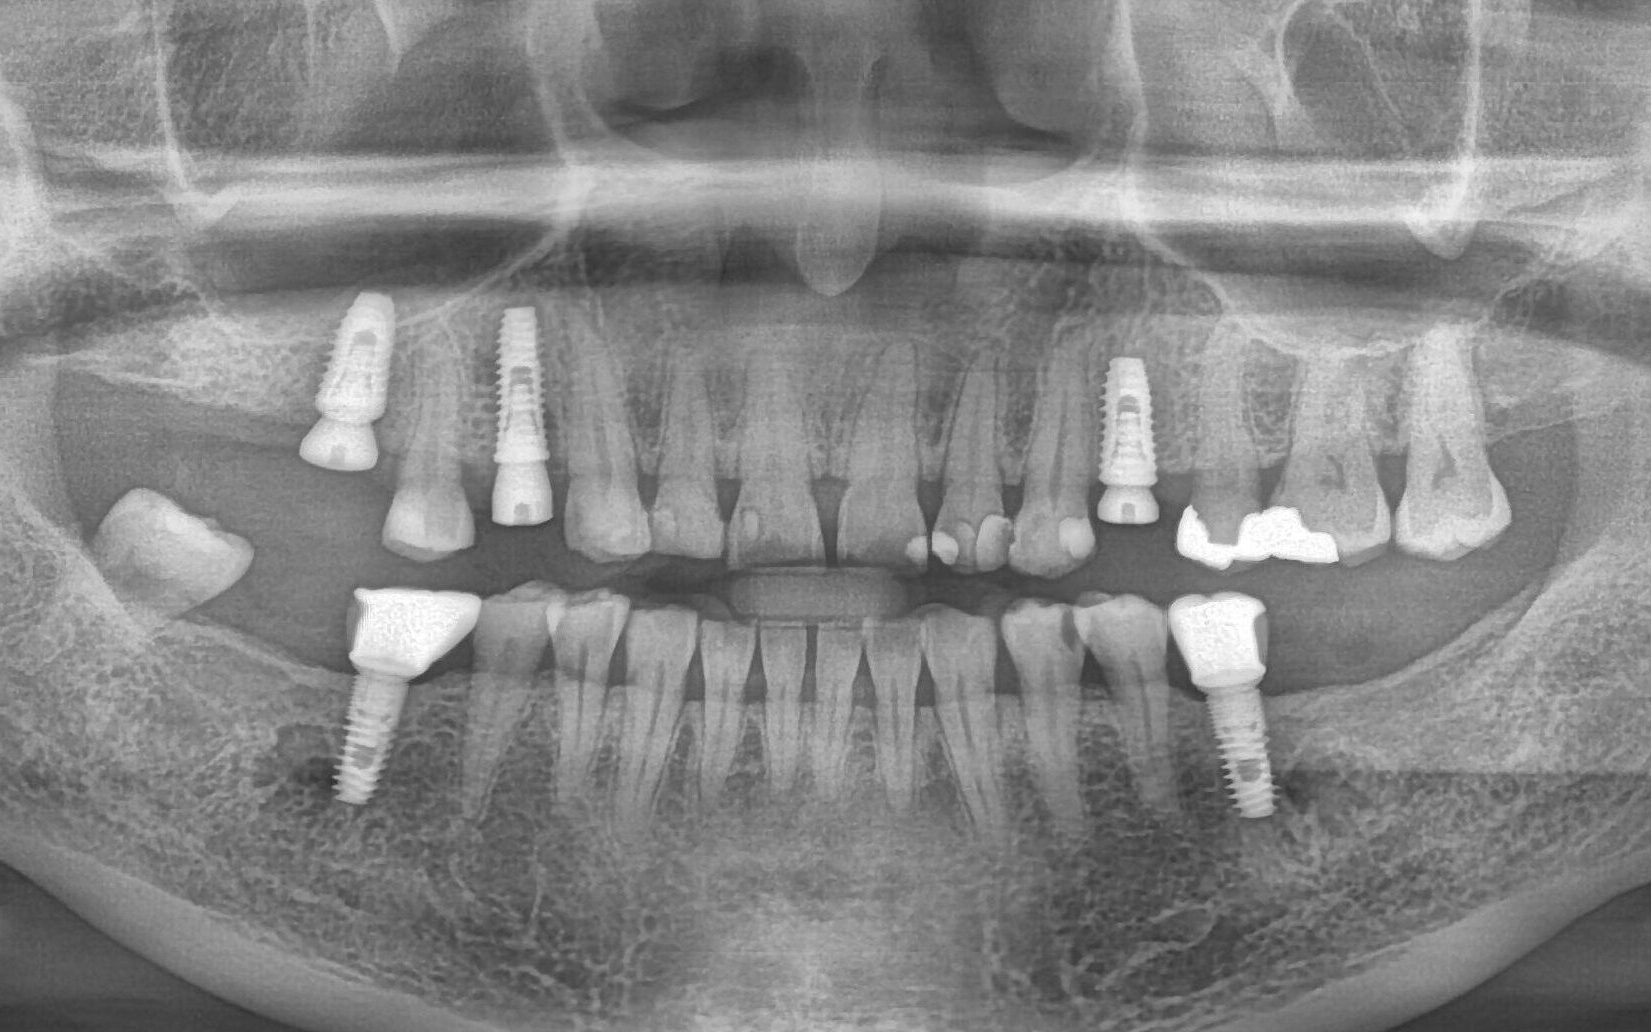

รากฟันเทียม (Dental Implant) เพื่อทดแทนฟันที่สูญเสียไป ให้ความรู้สึกใกล้เคียงกับฟันธรรมชาติมากที่สุด ซึ่งจะไม่มีผลข้างเคียงที่จะทำให้เกิดอันตรายในการปลูกรากฟันเทียม จำเป็นต้องให้ทันตแพทย์ที่มีความเชี่ยวชาญ

ผลงานบางส่วน ของทีมทันตแพทย์ของคลินิกเรา โดยได้รับอนุญาตให้เผยแพร่ ด้วยความเต็มใจจากผู้ป่วยขอบขอบคุณผู้ป่วยทุกๆท่าน

เครื่องเอกซเรย์ฟันนอกช่องปากระบบ 3 มิติ เทคโนโลยีทางการแพทย์ที่จะมาช่วยเพิ่มประสิทธิภาพในงานด้านทันตกรรม ครอบคลุมตั้งแต่การรักษาคลองรากฟัน ทันตกรรมรากฟันเทียม งานทันตกรรมทั่วไป จนไปถึงการผ่าตัดศัลยกรรมขากรรไกร และใบหน้า

การรักษารากฟันเทียมแบบดิจิทัล ที่ช่วยให้ทันตแพทย์สามารถวางแผนตำปหน่งรากฟันเทียมได้ตามความต้องการ โดยขึ้นอยู่กับความต้องการในการบูรณะรากฟันเทียม และเงื่อนไขของการผ่าตัด